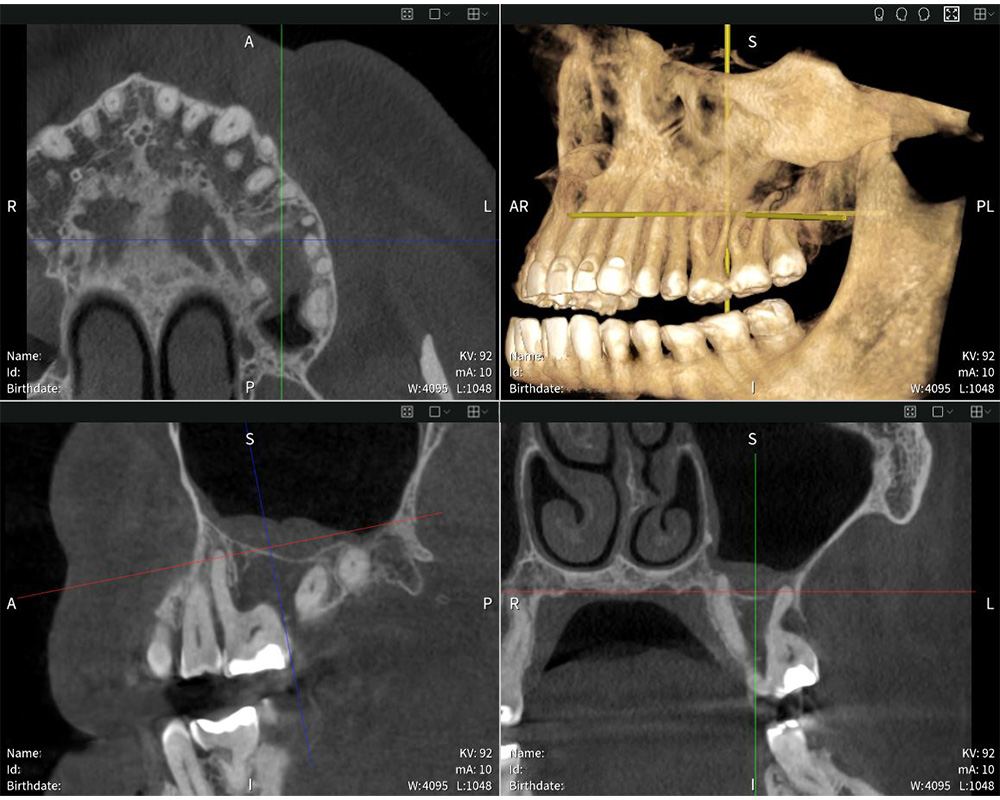

Obtención de imágenes precisas con Seethrough Max: La radiografía muestra la hinchazón de la mucosa del seno maxilar.

Obtención de imágenes precisas con Seethrough Max: La radiografía muestra la hinchazón de la mucosa del seno maxilar. © Dr med. dent. Mauro Amato